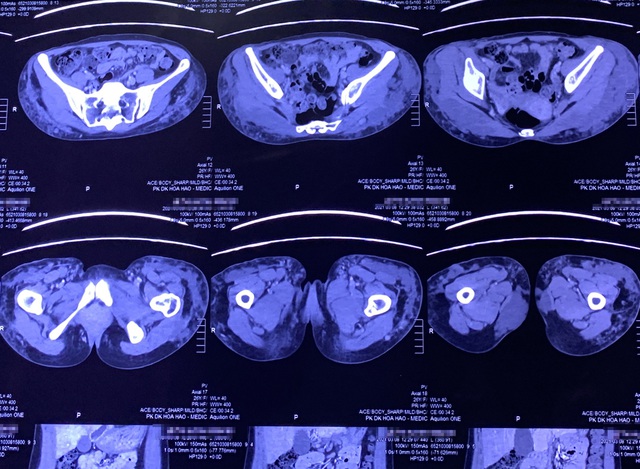

Hình ảnh kiểm tra của bác sĩ cho thấy những tổn thương nghiêm trọng ở vùng mông của người bệnh.

Qua thăm khám trực tiếp và chẩn đoán kết quả chụp MRI, bác sĩ Tú Dung phát hiện filler đã lan rộng khắp vùng mông trái của bệnh nhân, đến tận khu vực xương chậu, khiến cho mông bị sưng phồng, cứng ngắc, nhiều vùng bị vón cục. Nếu không điều trị khẩn cấp sẽ dẫn đến hoại tử. Ở giữa vùng biến chứng filler có vết thương sâu, liên tục chảy dịch, khiến bệnh nhân đau đớn. Ngay lập tức, bác sĩ Tú Dung chỉ định mổ khẩn nạo vét filler trong cơ thể bệnh nhân.